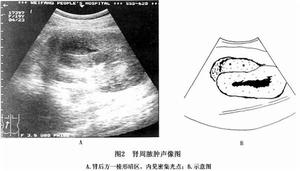

2.B超檢查可顯示腹膜後低回聲聲影以及膿腫的大小及範圍。有學者報告,該檢查敏感性約67%。